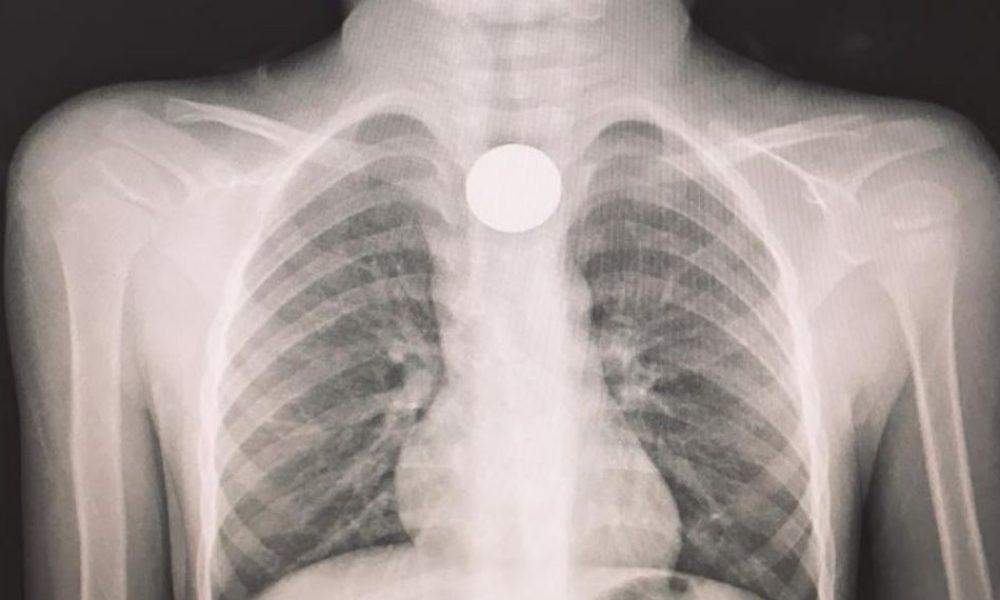

Giunto al pronto soccorso dopo aver ingoiato una moneta, viene trasferito in elicottero all’ospedale di Cosenza dove, dopo un tempestivo intervento, è stato dichiarato fuori pericolo.

“Si è conclusa positivamente la disavventura del piccolo A. M., 4 anni, italiano con genitori stranieri, che in mattinata era stato accompagnato al pronto soccorso dello Jazzolino. A dire dei familiari, il bimbo mentre giocava aveva probabilmente ingerito un corpo estraneo, poiché improvvisamente aveva smesso di parlare e si portava angosciosamente le mani alla gola.”